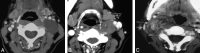

Results: The schwannomas were solitary, well-circumscribed, and medial to the carotid sheath. Seven were hypoattenuated to skeletal muscle on CT with poor postcontrast enhancement, 4 were isoattenuated, and a single lesion showed intense heterogeneous enhancement. At MR imaging, they were heterogeneously bright on T2WI with intense inhomogeneous postgadolinium enhancement. The ICA was displaced anteriorly in 9 patients with a component of lateral displacement in 8 of these patients. The ICA was in a neutral position in 2 patients and posterolaterally displaced in 1 patient. A single patient demonstrated separation of the ICA and IJV. There was splaying of the carotid bifurcation in 4 patients.